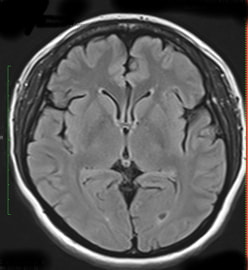

最初に問診を行います。必要に応じて検査を行い、その後、診察/検査結果を説明し方針を立てます。脳神経外科診療においてはMRI検査が頭蓋内評価に有用ですので、診察/診断の根拠のためにもキー写真をスナップショットでお渡しするようにしております。

頭痛/めまいなどは脳卒中や脳腫瘍などの初発症状のこともるため、MRIにて頭蓋内スクリーニングを行います。当日、結果説明します【理念2・4】。